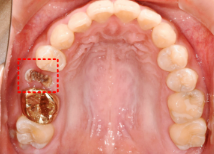

왼쪽 사진에 보시면 빨간색 네모 박스 보이시나요? 이 부분의 치아가 상실되어 임플란트가 필요한 상황이었습니다.

바로 옆에 있는 골드크라운 치아도 교체가 필요한 상황이라.. 임플란트와 골드크라운 교체를 함께 진행하기로 결정하셨는데요.

우측 엑스레이 보시면, 치아 뿌리가 남아있는 상황으로 '치아 뿌리 발치'가 먼저 필요한 상황이었습니다. 방치하게 되면, 통증이 더 심해질 수 있기에 빠르게 발치를 먼저 진행하셨습니다.